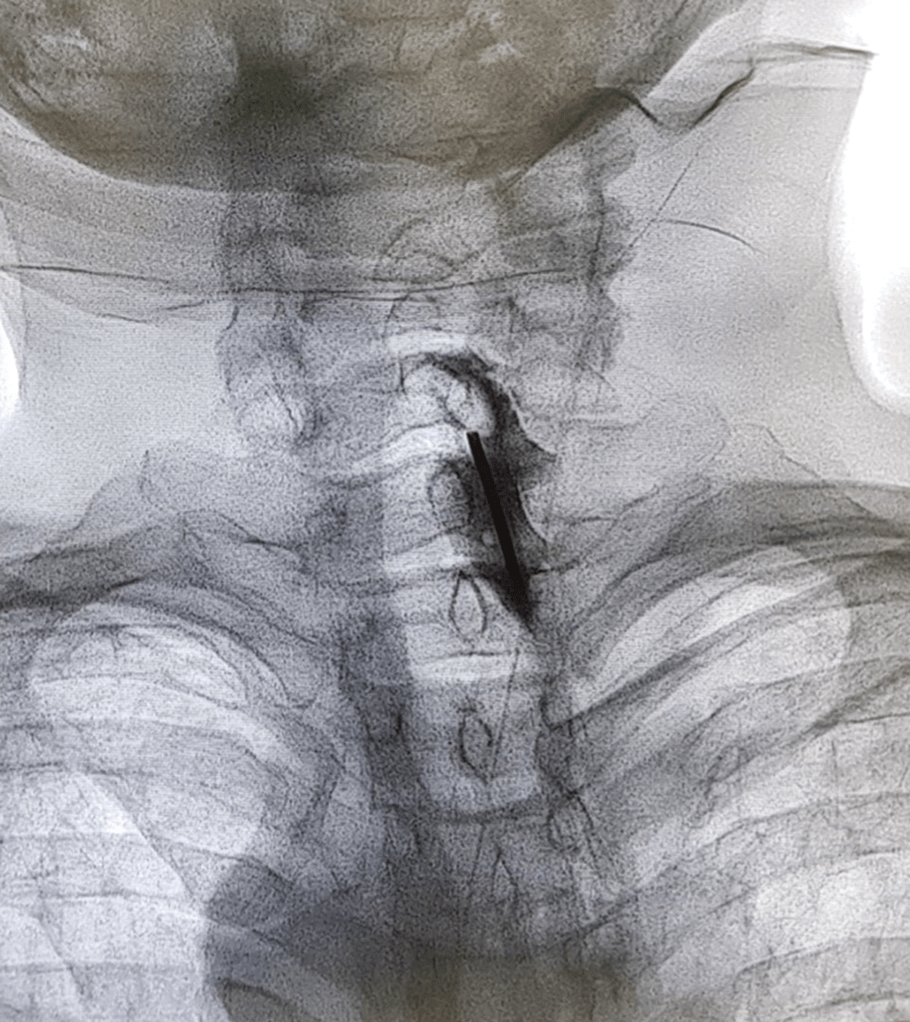

Cervical interlaminar epidural steroid injection (fluoroscopic guided

from radiopaedia.org